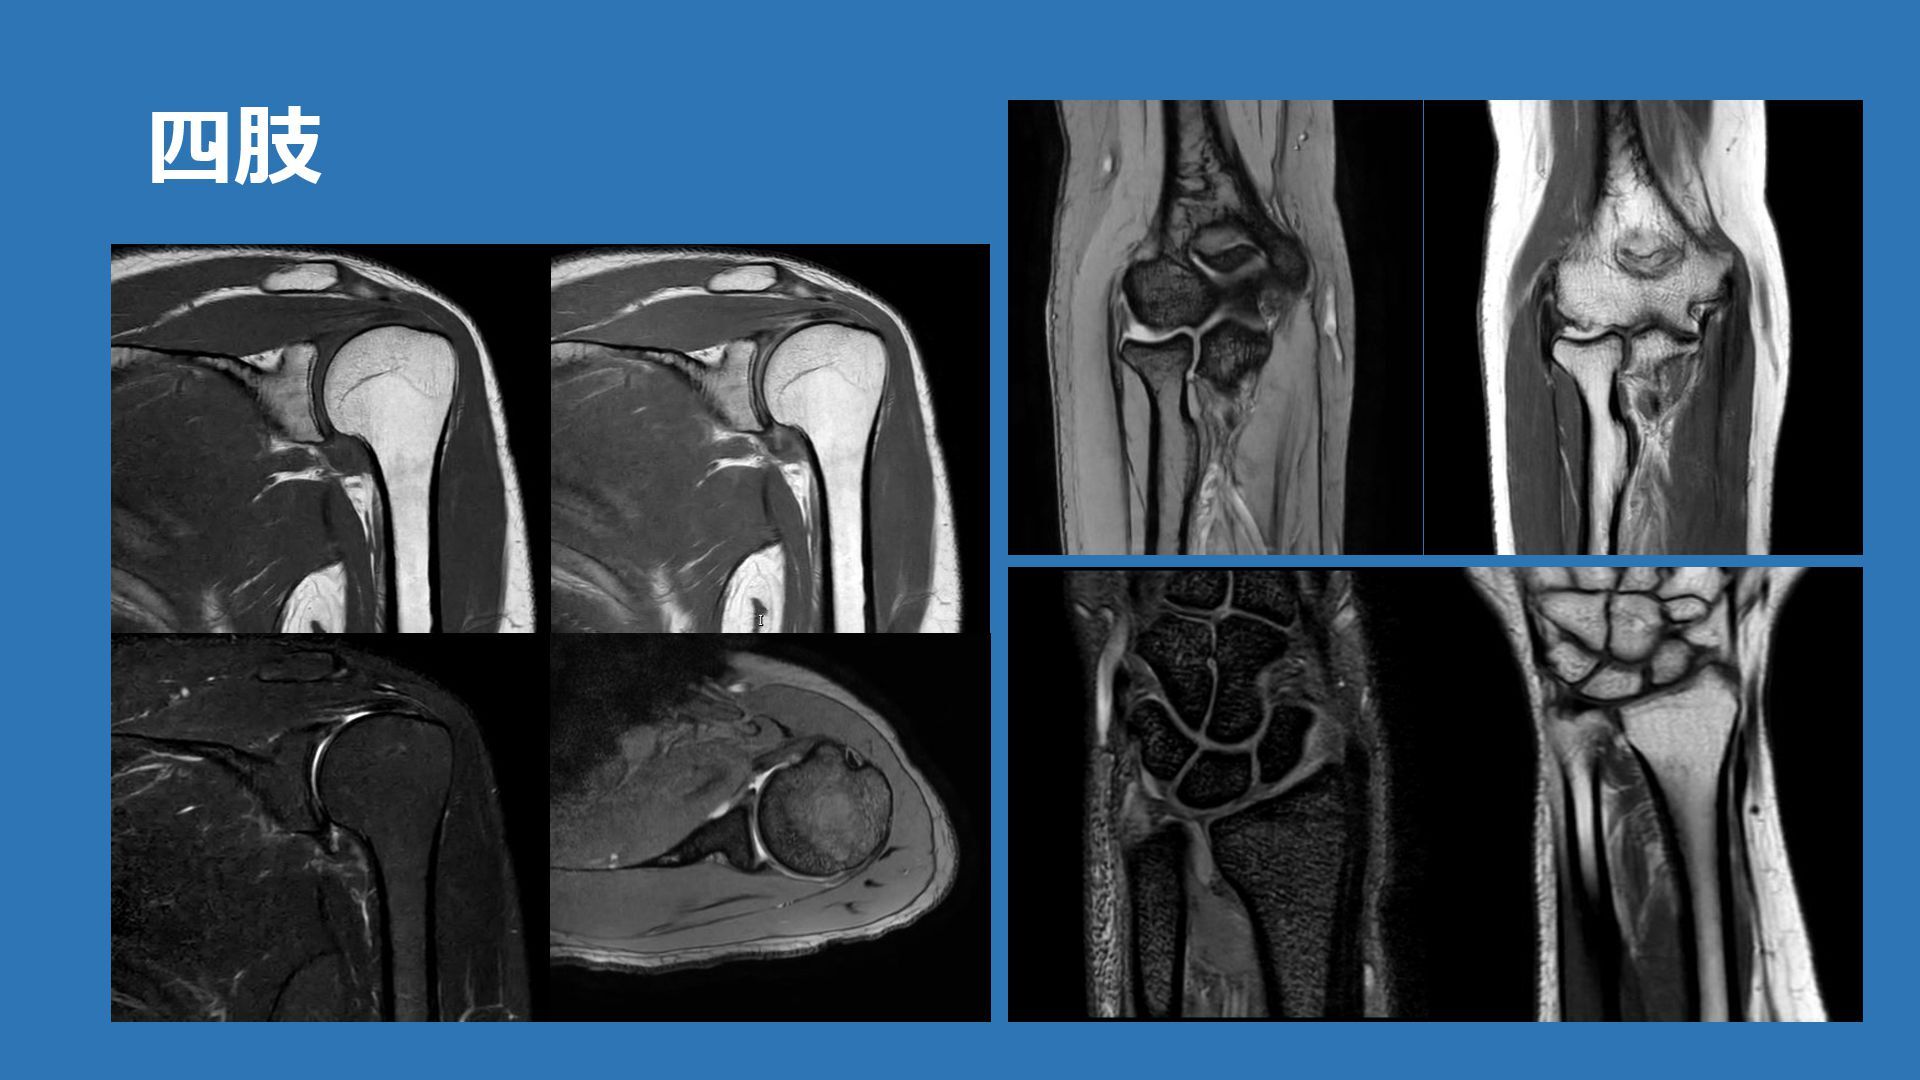

四肢